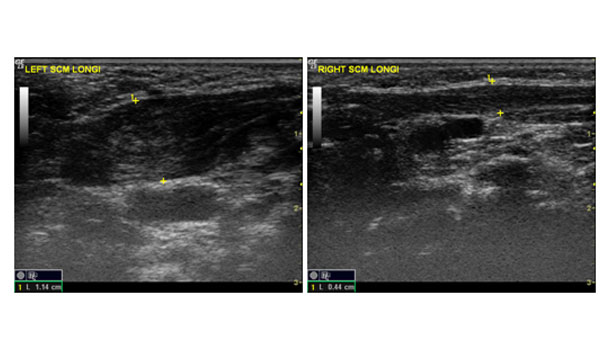

復健科門診可以做超音波檢查,做為治療預後的參考,以利擬定治療計畫。如果在超音波影像下,胸鎖乳突肌呈現全是纖維化的條狀組織,無正常肌肉組織,且復健治療效果不佳時,將來需要手術治療的機率較高。

| 胸鎖乳突肌的超音波影像,左圖為病兆處的胸鎖乳突肌,為一非均質性的肥大假性腫瘤,右圖為正常的胸鎖乳突肌。圖片來源:楊佩瑜醫師提供 |